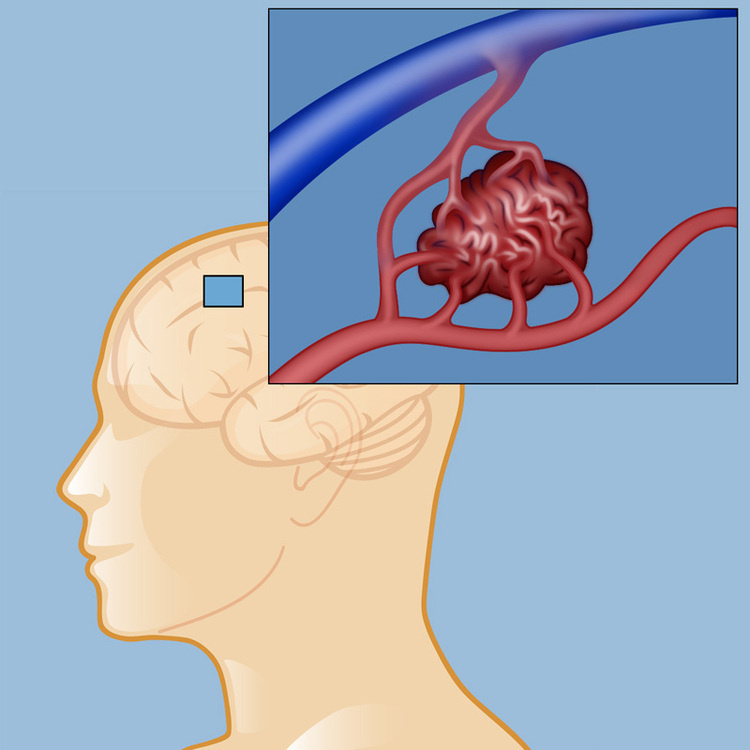

Tangled blood vessels in the brain affect thousands of people, yet many have never heard of arteriovenous malformations (AVMs). Weill Cornell Medicine's neurosurgery experts are at the forefront of innovative treatment approaches for these complex conditions. In this webinar, award-winning neurosurgeon Dr. Ning Lin will discuss the latest advances in AVM treatment and how modern surgical techniques, embolization, and radiosurgery are transforming care for patients with these brain blood vessel tangles. He will explain how each treatment approach works, which types of AVMs may benefit from different options, and provide insights to help patients and families better understand these cutting-edge treatment methods and what to expect during the care process. Whether you're experiencing unexplained neurological symptoms, have been recently diagnosed with an AVM, are supporting a loved one, or simply want to understand more about brain vascular health, this webinar will provide valuable insights from a leading neurosurgeon.